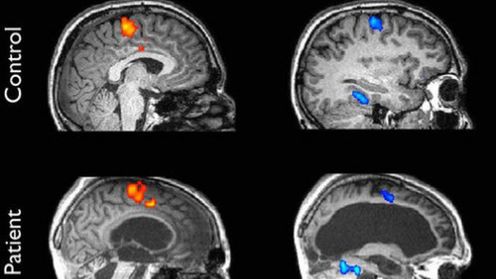

Przeprowadzone w Belgii badania, jak donosi New York Times, polegały na poddaniu pięćdziesięciu czterech pacjentów testom, w których mieli odpowiadać na zadane pytania poprzez wyobrażanie sobie konkretnej sytuacji: na przykład spaceru po ulicach domowego miasta lub uczestnictwa w meczu tenisowym. Pytania były sformułowane w ten sposób, by odpowiedź na nie mogła sprowadzić się do prostego "tak" lub "nie".

Badaniom poddano 54 pacjentów, z czego 24 nie było w pełni w stanie wegetatywnym, lecz posiadało minimalną świadomość. Wyniki okazały się intrygujące. U pięciu pacjentów, w tym u czterech teoretycznie pozbawionych możliwości myślenia, skan mózgu wykazał aktywność w momencie, gdy mieli udzielić odpowiedzi. Co więcej, jeden z pacjentów, który według dotychczasowej wiedzy medycznej miał być pozbawiony świadomości i zaawansowanych procesów myślowych, potrafił odpowiedzieć na stawiane pytania poprzez odpowiednie wyobrażenie. Pytano go na przykład o to, czy ma ojca o imieniu Thomas, odwołując się przy tym do jego wspomnień. Odpowiedzi były zawsze prawidłowe, a aktywność mózgu porównywalna z tą wykazywaną przez należących do grupy kontrolnej ludzi.